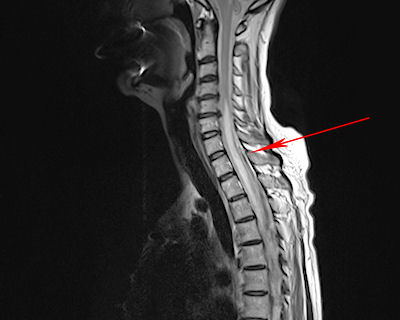

A Spinal Cord lesion

typical for MS

atypical for MS